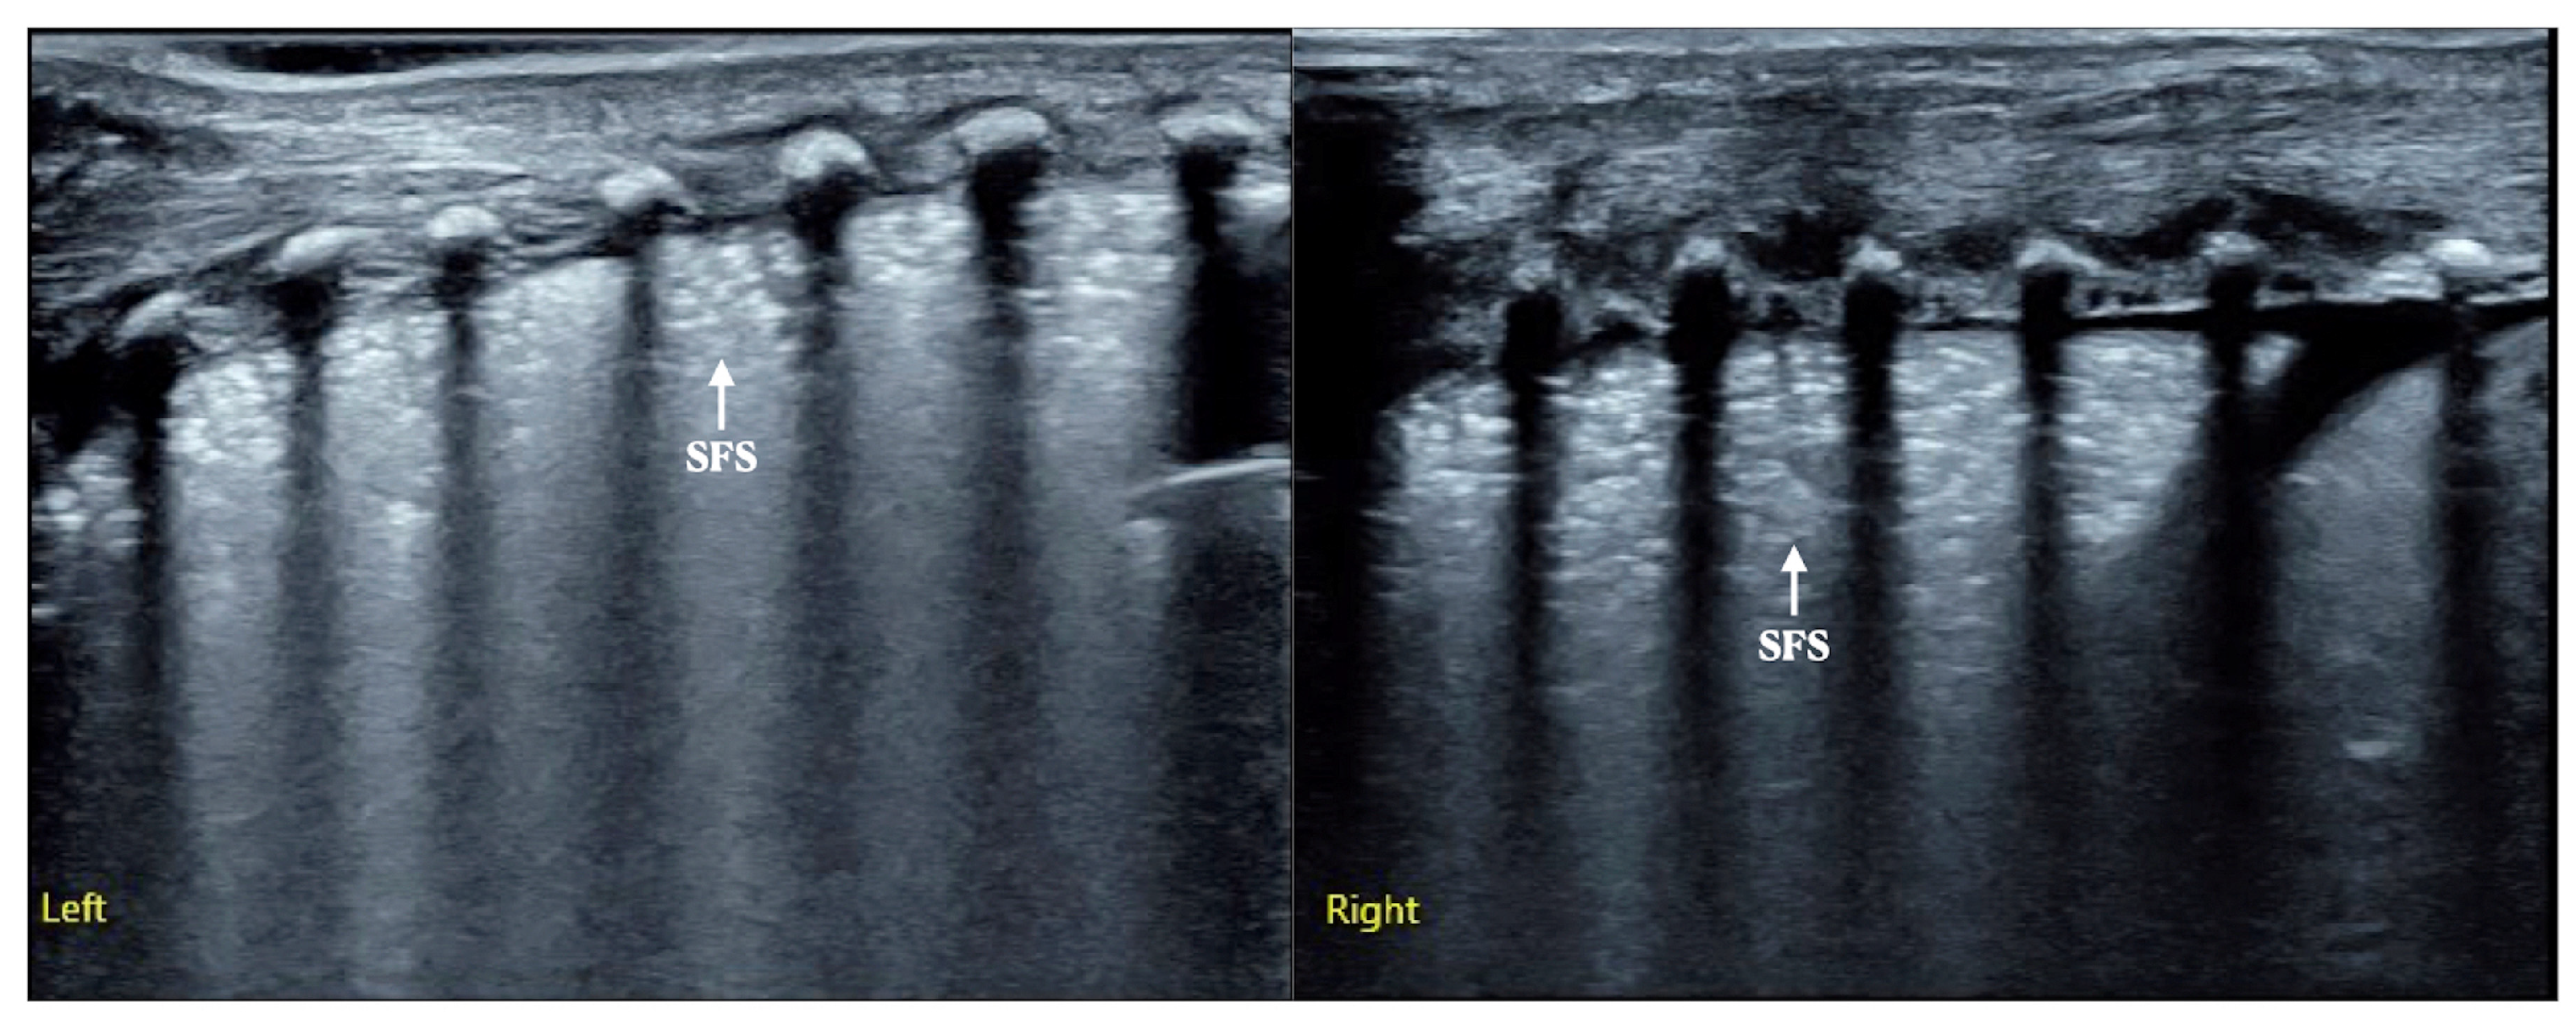

Case 2: This female baby was G1P1 with a gestational age of 31+4 weeks, vaginal delivery, and a birth weight of 1880 g. She was admitted to our NICU because of progressive dyspnea, significant expiratory moans and retraction for 1 h [Video S2]. Arterial blood gas analysis showed PaCO2: 56 mmHg, PaO2: 42 mmHg and SaO2: 79%. On admission, LUS examination showed snowflake-like sign (SFS) lung consolidation in the bilateral lungs, which was consistent with the typical ultrasound imaging characteristics of RDS [Figure 3].

Figure 3.

LUS findings of Case 2 infant. LUS presented as snowflake-like sign consolidation confirmed as RDS (Left: left lung, Right: right lung).